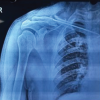

A 22-year-old male gave a history of pain and swelling in the left knee before 10 years for which he got radiologically diagnosed as synovial hemangioma and arthroscopic debridement and biopsy was done. Now the patient resulted in similar swelling and pain in the left knee which was dull aching pain and vague. The pain was aggravated on movements and relieved partially by rest and medications. On examination, the left knee swelling was tender, euthermic with boggy consistency, and synovial hypertrophy. The patient had a painful terminal range of movements of his left knee. The plain radiograph of the left knee was shown in (Fig. 1).